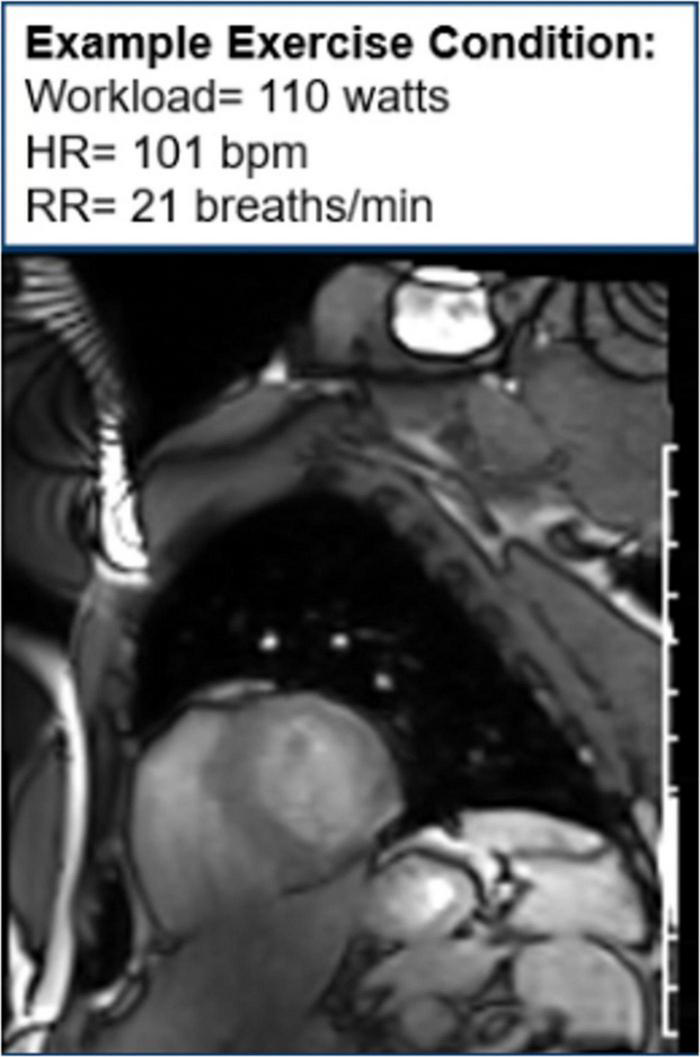

Moreover, CMR can be used to assess cardiac function during exercise testing (72) and has even been utilized in hematologic cancer survivors by placing an exercise bike in the magnetic resonance imaging (MRI) scanner (Figure 10). Cine images at rest and during exercise are depicted (Figures 11, 12), as this technology allows for myocardial function to be compared at baseline and during exercise (73).

FIGURE 11

Cine image at rest. One image of a cine loop at the end short-axis view of the myocardium. The left ventricle is gray, while the blood pool is white. At rest, the workload is 0 w, and the patient’s heart rate is 50 bpm and respiratory rate is 11 breaths/min.

FIGURE 12

Cine image during exercise. One image of cine loop at the end short-axis view of the myocardium. The left ventricle is gray, while the blood pool is white. During exercise, the workload is 110 w, and the patient’s heart rate is 101 bpm and respiratory rate is 21 breaths/min.